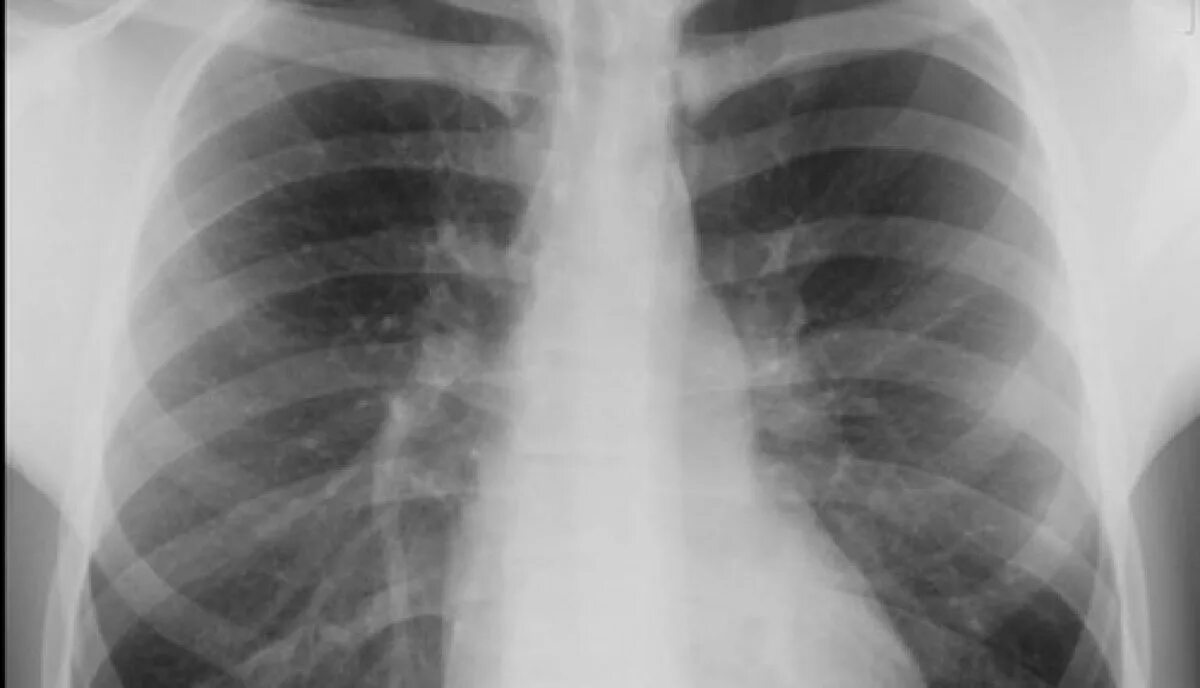

Множественные ребра